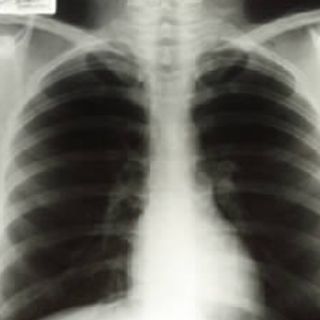

Estas placas que muestran la caja torácica de la actriz fueron tomadas dos semanas después de su divrocio con el jugador Joe DiMaggio

LOS ÁNGELES, ESTADOS UNIDOS (28/JUN/2010).- Tres radiografías tomadas a Marilyn Monroe dos semanas después de su divorcio del jugador de béisbol Joe DiMaggio fueron vendidas por 45 mil dólares este fin de semana en una subasta en Las Vegas, Nevada.

Las imágenes clínicas mostraban la caja torácica de la actriz así como uno de sus costados y alcanzaron en la puja un precio hasta 10 veces superior a lo estimado por la casa de subastas Julien's Auctions, que organizó el evento.

Las radiografías correspondieron a una visita al hospital Cedars of Lebanon de Los Ángeles en noviembre de 1954, 6 años antes de su fallecimiento.